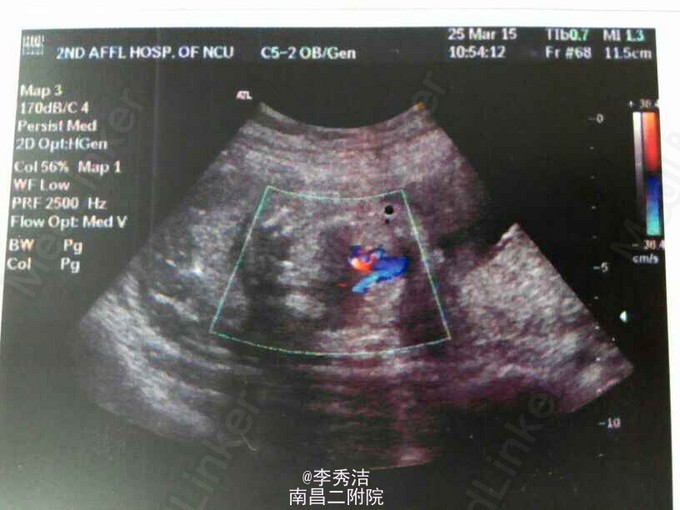

患者女,30岁,孕27周,一周前唐氏筛查提示高危,遂行羊水穿刺,发现胎儿为唐氏综合症患儿。给予引产处置术。 唐氏综合症又叫做21三体综合征,先天愚型,是说患者的第21对染色体比正常人多出一条(正常人为一对),是最常见的染色体非整倍体疾病。唐氏筛查是在特定孕周,通过检测孕妇血清中PAPPA、 AFP、HCG、uE3和Inhibin A的含量,结合孕妇的年龄,孕周,体重,是否吸烟,患有胰岛素依赖性糖尿病等临床信息,通过风险评估软件计算的风险值。 临界值为1/250-380(由于方法学的不同,可能此数值有所不同)。大于为高危,小于则为低危。普通人群(35岁以下)患有唐氏(DS)的概率为1/750。根据检查时间分为孕早期(9-13周)和孕中期(14-21周)。 唐筛检查,是唐氏综合症产前筛选检查的简称。目的是通过化验孕妇的血液,结合其他临床信息,来综合判断胎儿患有唐氏症的危险程度,如果唐筛检查结果显示胎儿患有唐氏综合症的危险性比较高,就应进一步进行确诊性的检查--羊膜穿刺检查或绒毛检查。